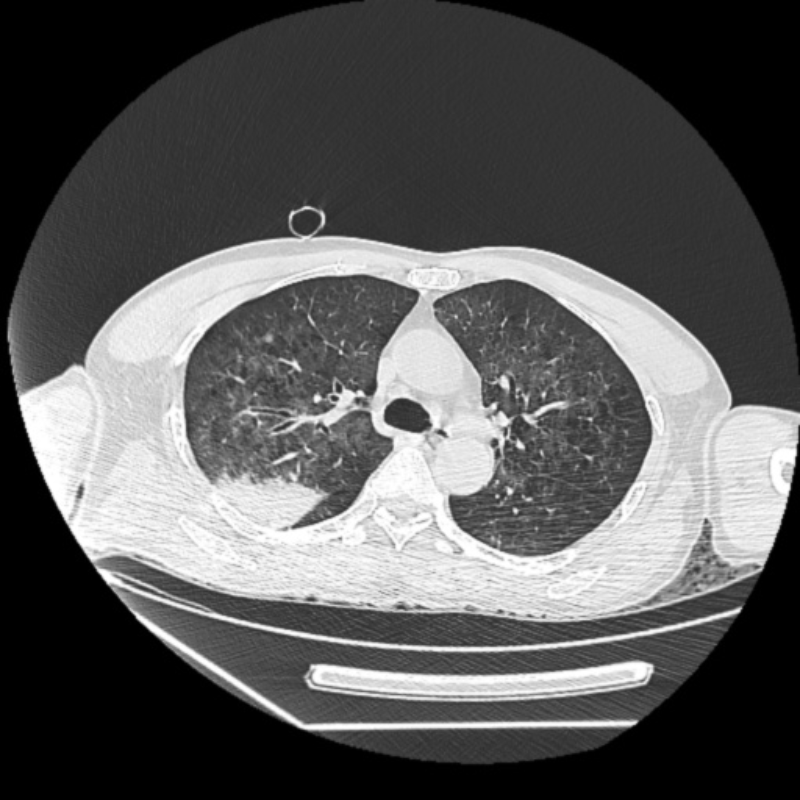

容伯伯到達急診醫(yī)學科急診搶救室后,還是神志昏迷、呼吸急促,心電監(jiān)測提示血氧飽和度低。急診搶救室吳文龍副主任醫(yī)師立即予以氣管插管接呼吸機輔助通氣治療,迅速完善血氣分析、CT等相關(guān)檢查后,擬“溺水”收入重癥醫(yī)學科。

容伯伯入住重癥醫(yī)學科后,值班醫(yī)生周明醫(yī)師給予雙肺纖維支氣管鏡檢查,鏡下所見氣道內(nèi)可見渾濁的液體,考慮患者在魚塘中溺水所致,周明仔細操作,反復灌洗,不斷吸引,把容伯伯雙肺的臟水污物清除干凈。重癥醫(yī)學科陳勁飛主任查看容伯伯病情,考慮魚塘中病原微生物條件復雜,指示抗感染予廣覆蓋常見的革蘭氏陰性菌、陽性菌、真菌等,同時患者心肺復蘇后,予加強低溫腦保護,機械通氣、化痰、加強其他臟器功能保護、營養(yǎng)支持等綜合治療……